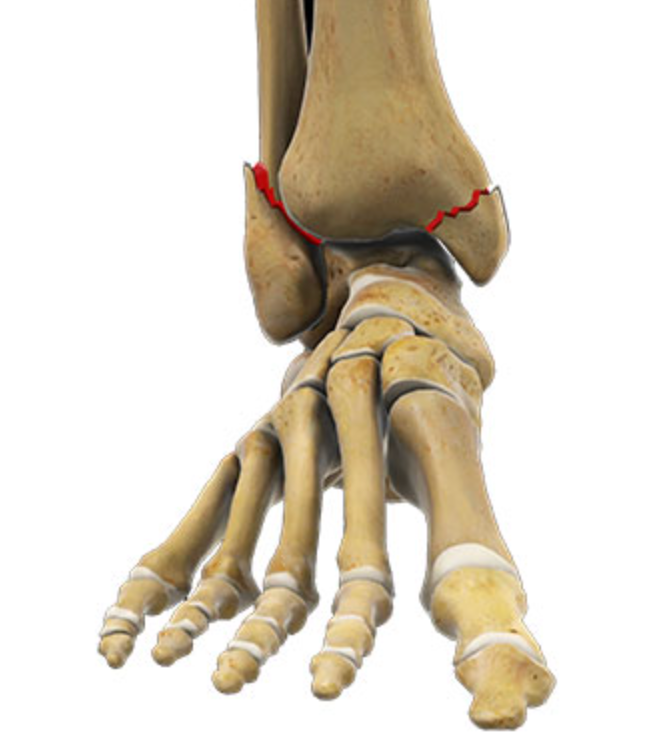

The ankle joint is made up of the tibia, fibula, and talus. The lower ends of the fibula and tibia connect and rest on the talus, which serves as the main link between the leg and foot.

- Lateral Malleolus Fracture: Occurs when the distal portion of the fibula breaks, affecting the outer side of the ankle. This is the most common type of ankle fracture.

- Medial Malleolus Fracture: Occurs when the distal portion of the tibia breaks, affecting the inner side of the ankle.

- Bimalleolar Fracture: This occurs when both the distal tibia and fibula are broken. It is the second most common type of ankle fracture.

- Trimalleolar Fracture: In this case, three parts of the ankle are fractured, most commonly involving the tibial malleolus, fibular malleolus, and posterior malleolus.